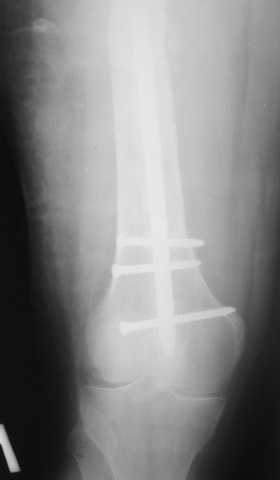

Мы демонтировали спице-стержневой аппарат, рассверлили костно-мозговой канал (до 14 мм), установили в канал спейсер с антибиотиком и произвели его блокирование четырьмя винтами ( рис. 1, 2, 3, 4).

В качестве армирующего элемента для спейсера мы использовали титановый неканюлированный штифт типа UFN (диаметр 9 мм, длина 400 мм). Проксимальную широкую часть штифта костным цементом не покрывали (рис. 5).

Дистальные блокирующие отверстия в цементе рассверлили после его застывания под ЭОП'ом. В проксимальном отломке использовали винт-полер (так как штифт проходил очень близко к переднему кортикальному слою).